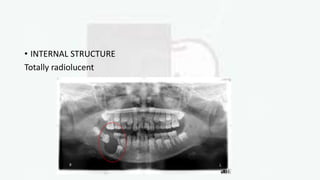

• INTERNAL STRUCTURE

Totally radiolucent